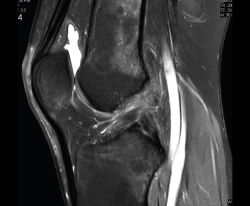

1.2.2. Ligamento cruzado anterior (LCA) (Figuras 40, 41, 42, 43 y 44)

Figura 40. Corte de secuencia sagital T2 Fat-Sat de resonancia magnética de rodilla: ligamento cruzado anterior normal.

Figura 41. Cortes de secuencia sagital T2 Fat-Sat de resonancia magnética de rodilla: rotura central del ligamento cruzado anterior.

Figura 42. Cortes de secuencia sagital T2 Fat-Sat: rotura proximal del ligamento cruzado anterior.